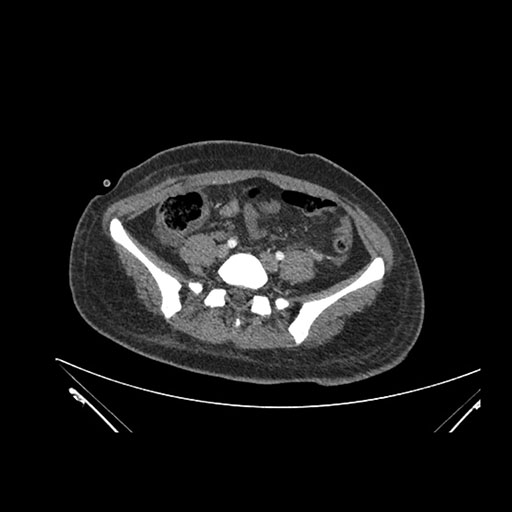

Imaging Analysis

Look through the patient's CT scan to identify any areas of concern for the necessary procedure.

Coronal Venous

Based on initial findings, which issue(s) would you be most concerned about?